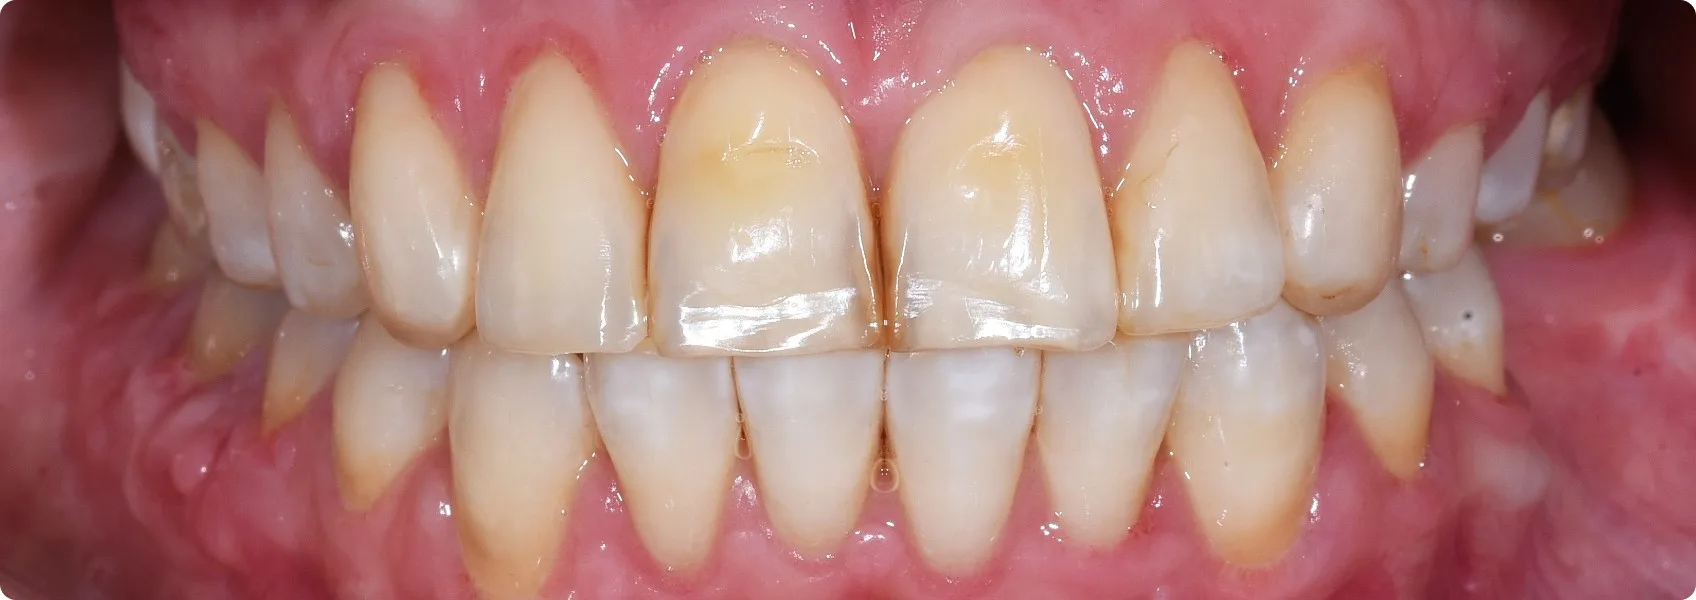

Nareszcie montaż licówek — najważniejsza chwila całego leczenia.

Efekt leczenia to nie przypadek. To wynik dziesiątek przemyślanych decyzji, precyzyjnej diagnostyki, współpracy lekarza z technikiem i ogromnego zaufania ze strony Pacjentki.

Od pierwszej konsultacji, przez planowanie cyfrowe, projektowanie uśmiechu, gingiwektomię, wax-up, mock-up, prowizorium i try-in — każdy etap miał znaczenie. Każdy był potrzebny, by rezultat był nie tylko piękny, ale też funkcjonalny i trwały przez lata.